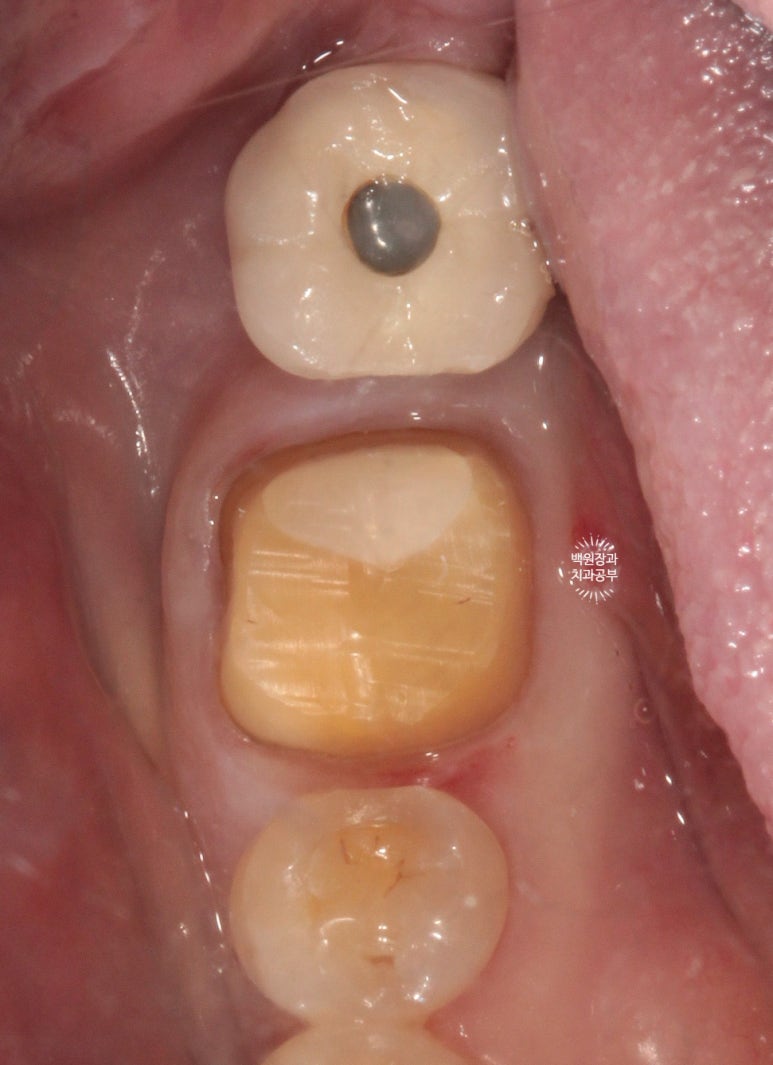

보시면 뒤에 위치한 임플란트의 치아 (구멍 있는 치아)와 앞에 위치한 작은 어금니와 넓은 접촉면을 형성하고 있는 것을 보실 수 있을거에요!

보철물은 치아에 비해 불완전하여 음식물이 쉽게 낍니다. 최대한 넓은 면적으로 접촉면을 형성해주는게 중요해요.

보철물 완성 6개월 후 촬영한 교합면 사진입니다.

특이하게도 좌우 어금니 부위가 맨 뒤의 임플란트 크라운 1개와 지르코니아 크라운 1개가 인접해있는 모양이네요.

지르코니아 크라운은 컴퓨터로 디자인하여 제작하기 때문에, 예로부터 많이 쓰이던 PFM 크라운 혹은 골드 크라운보다 훨씬 자연치아의 모양을 잘 모방하고 있으며 색상도 자연스럽습니다.

주변의 치아들과 상당히 조화로운 색상을 보이고 있고,

그 경계가 잇몸의 경계와 완전히 일치하여 훌륭한 결과를 보여주고 있습니다!!